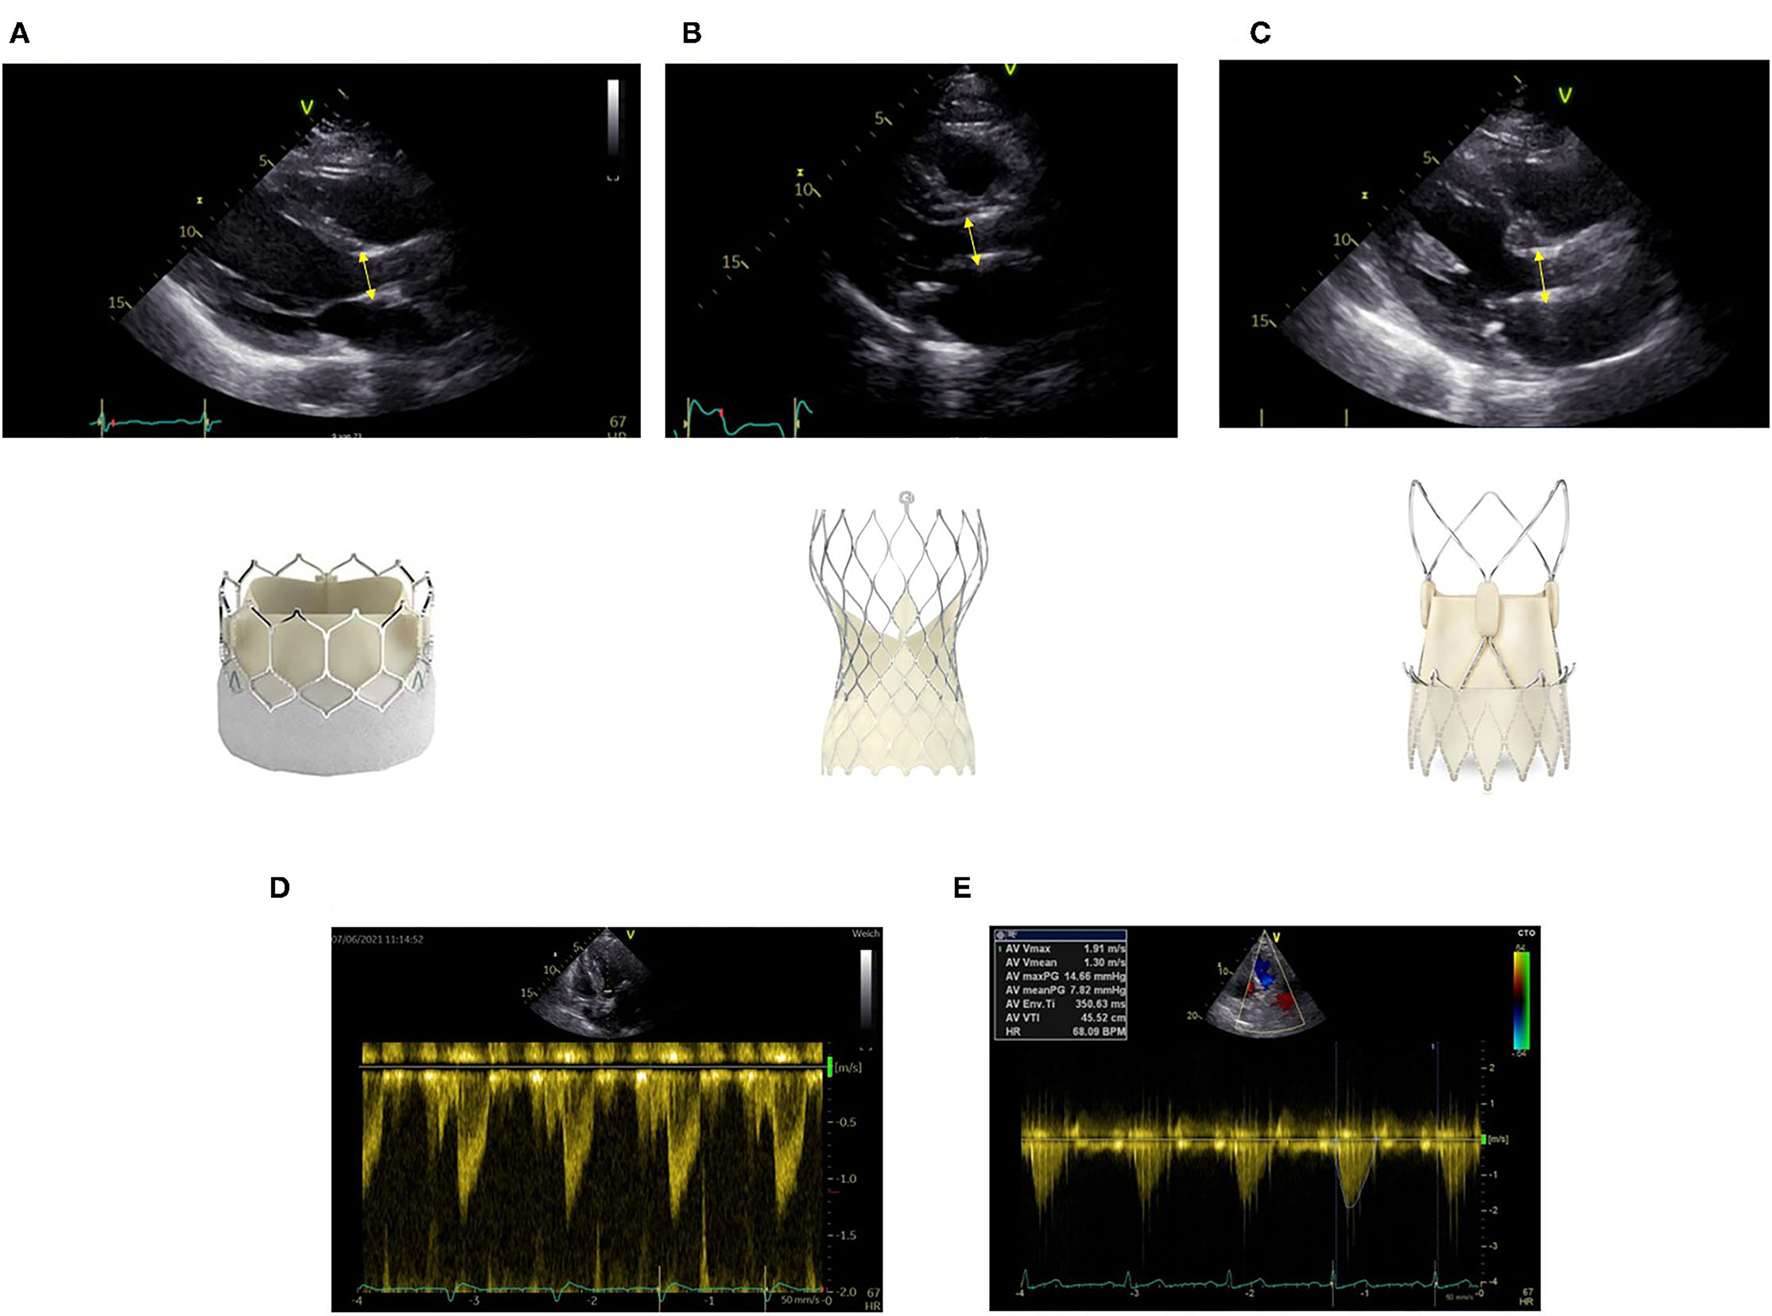

Due to the design of the transcatheter heart valves, there are two areas of flow acceleration: first at the level of the inferior edge of the stent and second at the level of the cusps. For correct measurement, it is crucial to measure LVOT diameter at the inferior edge of the stent (Figure 1A). It is important to measure from outer-edge to outer-edge. The different valve stents may challenge the echo-based LVOT measurements (Figures 1A–C). Echocardiographic measurements have to be made precisely. Potential measurement errors of the continuous and pulse wave Doppler signal need to be excluded (Figures 1D,E).

FIGURE 1

www.frontiersin.org

Figure 1. Correct measurement of left ventricular outflow tract (LVOT) diameter at the inferior edge of the stent as indicated by the yellow bar in different transcatheter aortic valve implantation (TAVI) prostheses (A) Sapien Ultra, (B) Evolut Pro, (C) Acurate neo2. Positioning of the pulse wave Doppler sample at the same level (D). Obtainment of highest peak velocity by continuous wave Doppler (E).